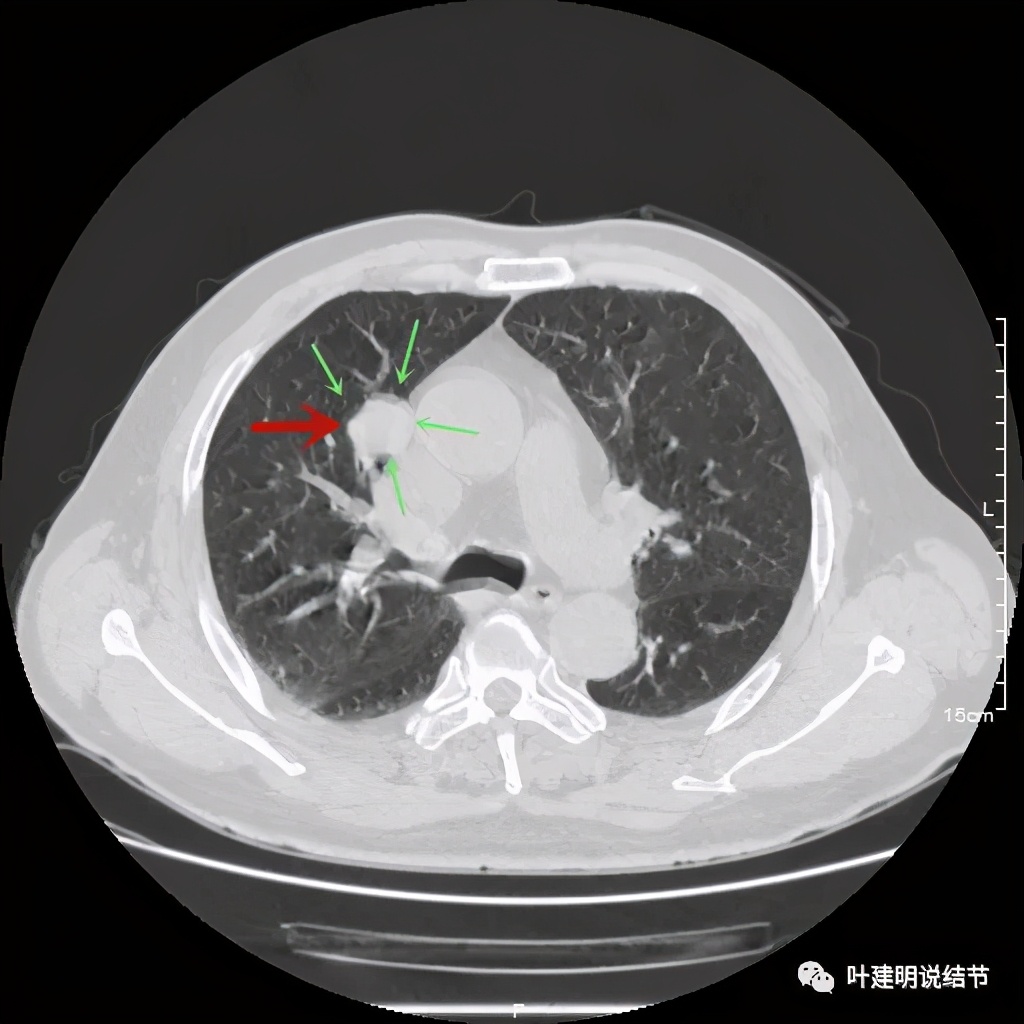

上图示病灶密度不均,但边缘过于光滑(绿色);支气管似有截断(粉色);局部有点状钙化(蓝色)

上图也示病灶密度不均,但边缘过于光滑(绿色);支气管似有截断(粉色);局部有点状钙化(蓝色)

病灶在上图层面似见支气管也是贴壁的。那么增强后又是如何呢?

上图示病灶边缘过于光滑(绿色);局部有点状钙化(蓝色)